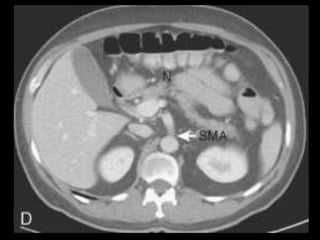

PÂNCREAS-VASOS

AORTA

TRONCO CELÍACO

MESENTÉRICA SUPERIOR

ESPLÊNICA

PANCREÁTICA DORSAL, MAGNA E TRANSVERSA

PANCREATICODUODENAIS SUP E INF

VEIA PORTA